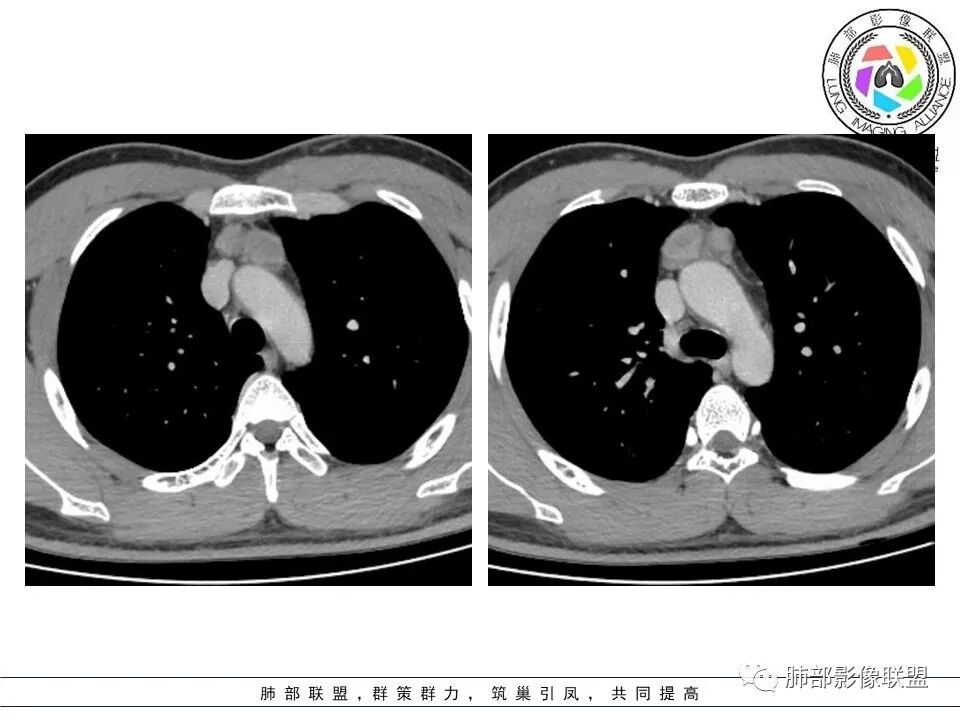

青少年男性,无症状,体检发现,前纵隔多个软组织结节影,边界尚清晰,密度不均,增强扫描轻度不均匀强化,考虑胸腺增生,鉴别:淋巴瘤(结节融合不明显,放第二吧),生殖细胞瘤(年轻人要考虑,需查AFP),纵隔结核(没肺窗,不知道肺上情况如何),其它如胸腺瘤,转移瘤等,一般发病年龄偏大,有原发肿瘤史,估计可能性不大。

胸腺增生pk淋巴瘤,16 男,发病年龄两个都符合。支持胸腺增生证据 :

1 结节基本按左右叶分布,没有明显横跨中线的结节

2 结节形态基本类肾型,低张力状态?

3 结节周围有密度稍高的胸腺背景(区别于淋巴瘤) 磁共振正反相位估计有帮助

支持淋巴瘤证据:  左侧有结节凸于胸腺形态外,有无价值,待验证  综合  胸腺增生可能大

良孑: 有环状强化,年青患者,首选TB,其次淋巴瘤

空格: 部分结节DWI高,T2有积液,不符合胸腺增生,还是淋巴瘤优先考虑。CT增强有环形强化。但DWI病灶中央也亮的,结核可能不大。

炎症:符合点——强化、周围边界不清,白介素6高,但是没症状,DWI中央低强化区不高

增生:符合点——整体内部结构松散,不符合点强化,白介素6高

关键在于其结构松散,外周密度增高,周围渗出